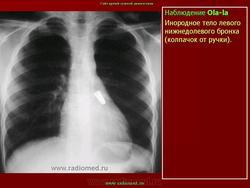

Инородные тела